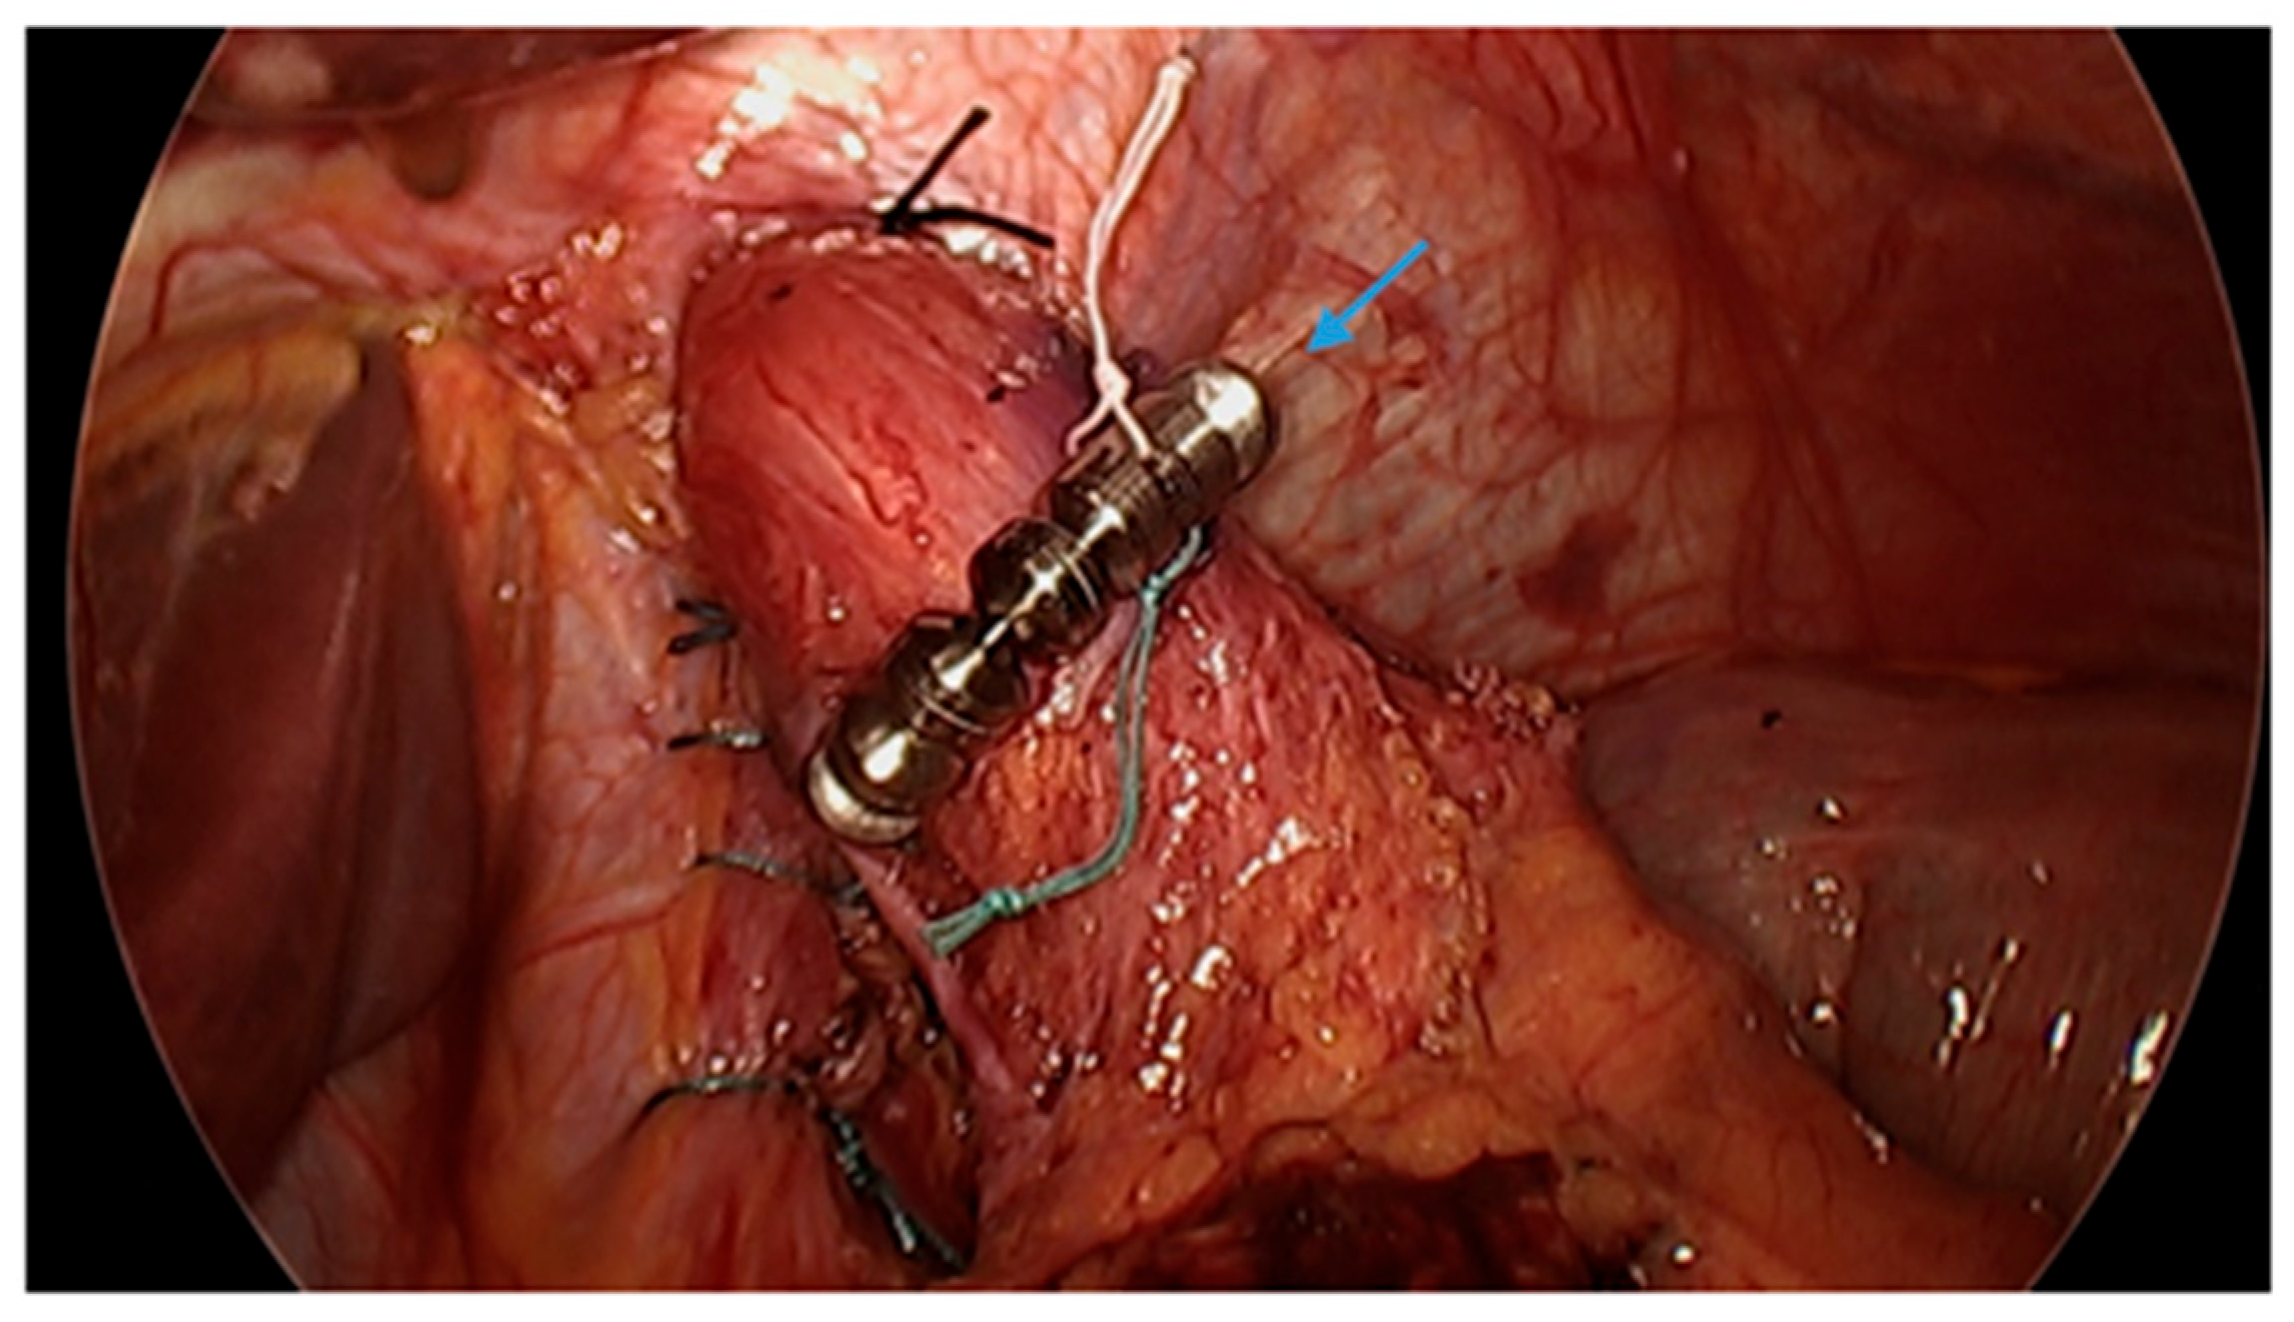

Figure 10.

Laparoscopic image demonstrates hiatal hernia repair and successful placement of a magnetic sphincter augmentation device (arrow) around the esophagus in a patient post-sleeve gastrectomy with gastroesophageal reflux disease. Image courtesy of Dr. Brian Louie, Chief of Thoracic Surgery at Swedish Medical Center in Seattle, Washington, USA.